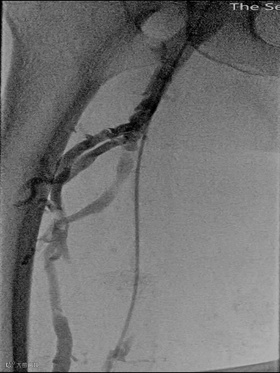

手术过程